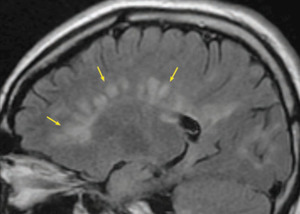

11/ "Dawsonβs Fingers" β Multiple Sclerosis (MS)

π Periventricular, ovoid white matter lesions oriented perpendicular to the ventricles.

π₯οΈ MRI FLAIR β Seen in MS due to perivenular demyelination.

β Key diagnostic feature for MS (McDonald criteria).